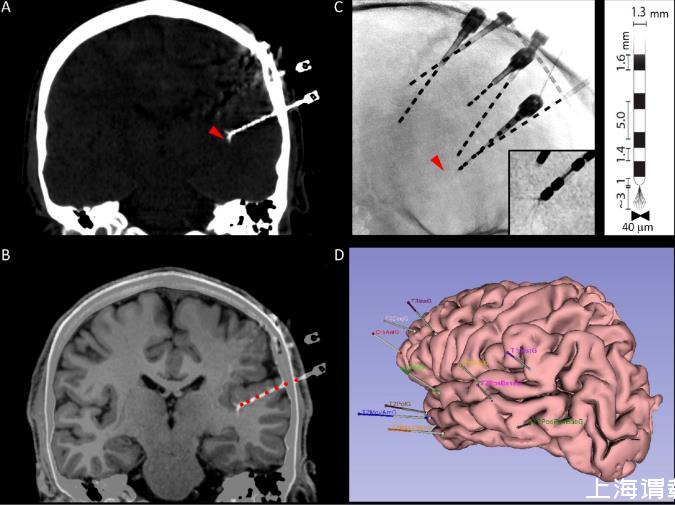

圖1.多模態微電極識別。A.冠狀面的顱骨計算機斷層掃描(CT),顯示了宏觀電極的軌跡以及微電極束的位置(紅色箭頭)。B.CT掃描與解剖學T1磁共振成像(MRI)的自動疊加,使得能夠可視化微電極在腦實質中的位置,同時還能自動識別沿腦內軌跡的宏觀電極接觸點(紅色圓圈)。C.放射影像顯示了腦內電極的二維位置。紅色箭頭指示了一個微電極束的位置,在前幾張中可見。插圖:微電極導線的放大圖。注意微導線的散開情況。右側插圖:宏觀-微電極幾何形狀的示意圖。D.受試者皮質解剖結構的三維Epiloc解剖重建,顯示了腦內宏觀電極的植入方案。

顱內電極的立體定向植入在神經外科進行。在將微電極插入專用的空心宏觀電極之前,神經外科醫生會將微導線剪至規劃期間確定的所需長度(通常為2-3毫米,補充圖1)。使用Yasargil顯微剪刀將它們全部剪成相同長度,并且垂直于電極軸,然后輕輕向外彎曲,直到它們形成像“傘”一樣的散開模式,當它們在腦內伸展時這種模式會保持(圖1)。這種散開模式提供了更好的記錄動作電位的機會。所有電極都用空心螺釘固定在顱骨上,以防止術后電極移動(錨定螺栓長度13毫米,以及LSBK1-AX-06,長度21毫米)。一旦所有顱內電極都植入后,用肥皂、水和聚維酮碘清潔并消毒患者的皮膚。然后對頭部進行處理,為長期視頻腦電圖記錄做準備,并仔細包扎(圖2和表1),這對于避免對電極造成任何損壞以及提高患者住院期間的舒適度是必要的。

植入后總是會進行術后計算機斷層掃描(CT)和磁共振成像(MRI),并與術前MRI進行融合,以驗證電極的位置(見2.6.2)。還會進行X光檢查,以確認微電極是否散開。